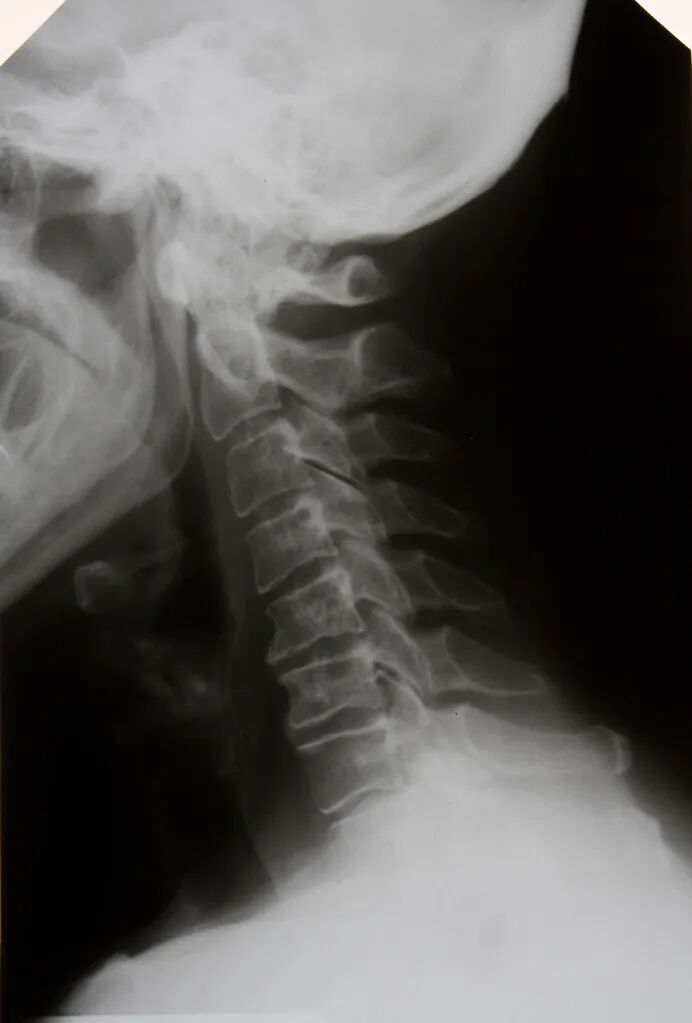

骨质疏松是一种常见的骨骼疾病,它会使骨骼变脆,易于断裂。很多老年人都会患上这种疾病,这也是他们感到后背疼痛的原因之一。

在日常生活中,我们会不断地用背部承受各种重力。如果我们的骨头变得松弱或脆弱,就会对背部造成压力。随着年龄增长,后背部的骨头就更容易断裂,这也就是为什么老年人后背常常会感到疼痛的原因。